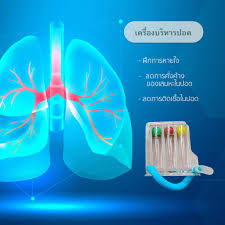

การออกกำลังกายฝึกการหายใจด้วยเครื่อง Incentive Spirometer (IS)

แบบ Triflow หรือ Tri ball

เป็นอุปกรณ์ที่ใช้ในการบำบัดเพื่อให้ปอดขยายตัวได้อย่างเต็มที่ ซึ่งถูกออกแบบมาทำให้เกิดการถอนหายใจหรือการหาวโดยการให้ผู้ป่วยหายใจเข้าอย่างช้าๆจนรู้สึกว่าหายใจเข้าลึกจนสุดเต็มที่แล้ว โดยมีลูกบอลเป็นตัวแสดงระดับความสามารถของผู้ป่วยเมื่อฝึกหายใจได้แรงพอลูกบอลใน Triflow จะลอยขึ้นสูงสุดและลอยค้างนานที่สุดเพื่อให้ได้ปริมาตรอากาศเข้าปอดได้เต็มที่คือให้ flow สูงสุดอย่างต่อเนื่องเป็นระยะเวลานานที่สุด

ประโยชน์ในการใช้เครื่องบริหารปอด ชนิด Triflow

- 1. เพิ่มปริมาตรปอด

- 2. เพิ่มการระบายอากาศ

- 3. เพิ่มการแลกเปลี่ยนก๊าซ

- 4. ทำให้เกิดรูปแบบการหายใจที่ถูกต้อง

- 5. กระตุ้นให้ปอดขยายตัวมากขึ้น

- 6. ส่งผลให้เสมหะถูกขับออกมาได้ง่าย

- 7. ป้องกันและรักษาภาวะแทรกซ้อนที่มักจะเกิดขึ้นหลังผ่าตัด เช่น ปอดแฟบ ปอดอักเสบ และเสมหะคั่งค้าง